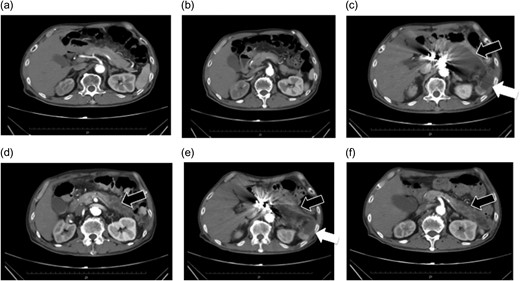

Preoperative enhanced computed tomography. (a and b) A saccular aneurysm can be observed on the descending aorta. (c) The aneurysm is very close to the celiac artery (arrow: origin of the celiac artery). The length of the celiac trunk is 11 mm. (d) The distance to the SMA is 21 mm (arrow: origin of the SMA). No endoleaks were noted in the aneurysm.